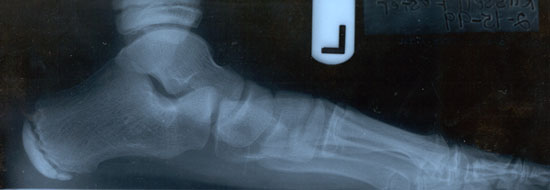

As seen in the photos above of the

x-rays, you can see the serious collapse in the foot before

treatment. In the photo on the bottom, we see an x-ray with

correction. Even though many doctors will still say that flatfeet do

not need to be treated, we know that this is not the case and the

current biomechanical literature now strongly supports treatment of

severe cases. In fact, this condition accounts for significant

skeletal problems later in life including: low back pain, knee joint

degeneration, increased risk of knee injuries, lower extremity pain,

and ankle problems.